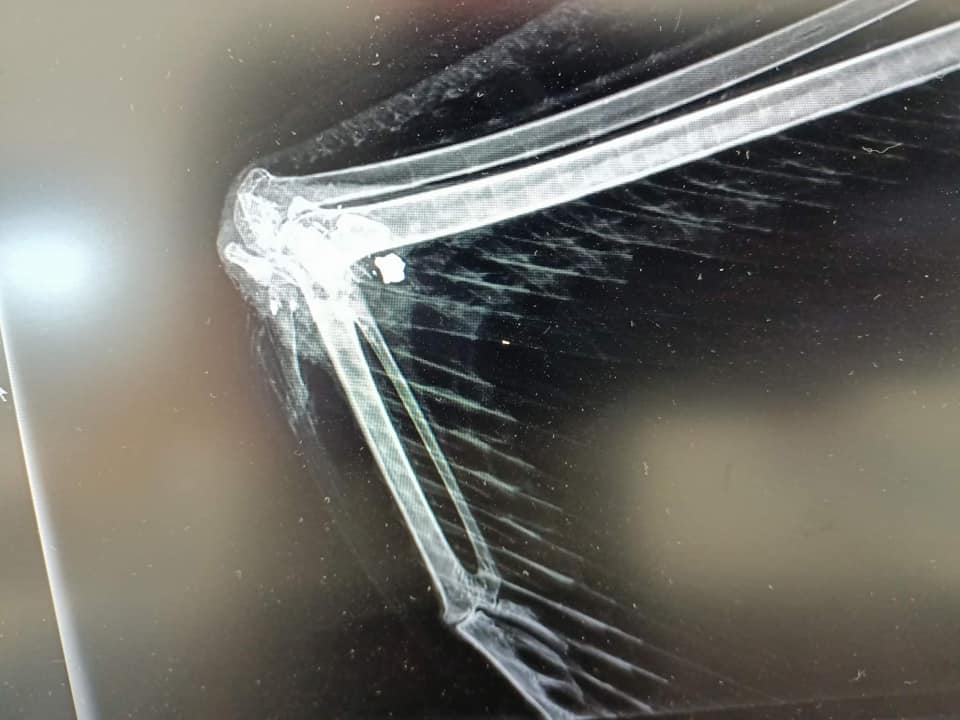

Ktoś strzelał z wiatrówki do bociana. Ptak na szczęście przeżył, ale niestety już nigdy nie będzie latał.

Do Leśnego Ośrodka Rehabilitacji Zwierząt Nadleśnictwa Piotrków, trafił bocian ze strzaskanym skrzydłem.

– Sądziliśmy, że to nieszczęśliwy zbieg okoliczności. Zastanawiające tylko było to, że w ostatnim okresie nie było silnych wiatrów. Zaskoczeniem okazała się rana postrzałowa skrzydła i odłamki śruciny, które nasza Pani weterynarz wyjęła ze skrzydła. Niestety postrzał zniszczył staw ” dłoni” lewego skrzydła i nie udało się go uratować. Ptak pozostanie w osadzie jako opiekun młodych boćków. – informuje Paweł Kowalskim z Ośrodka w Kole. – Nie możemy zrozumieć, dlaczego ktoś strzelał do ptaka? – dodaje leśnik.